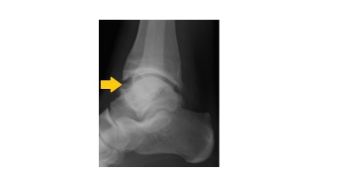

gelenkinstabilitaet

Instabiles Sprunggelenk das bei Belastung außen aufklappt (Pfeil) © Asklepios

Dehnungen, Zerrungen und Risse der Bänder im oberen Sprunggelenk (Bild oben) sind bei Umknicktraumen im Sprunggelenk häufig und können unbehandelt zu immer wiederkehrenden Folgeverletzungen der gleichen Art führen. Dies ist besonders problematisch, wenn sich der Patient an das Umknicken gewöhnt hat und mit instabilem Gelenk seine Sportarten weiter betreibt. Durch die vermehrten Scherkräfte kann es dann zu einem vorzeitigen Abrieb des Gelenkknorpels  kommen (Bild unten), was zu einer Arthrose oder Gelenkverschleiß führt.